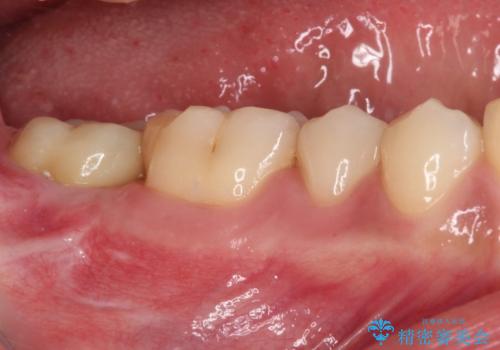

銀歯の頃は頻繁に外れていたため、不快感が強かったようですが、歯冠長を延長したことで外れにくいクラウンを装着することができ、不快感が改善されました。